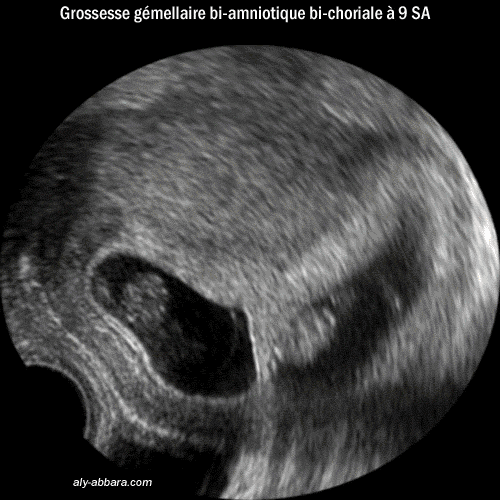

- Image échographique montrant

le type de placentation en cas de grossesse gémellaire bi-amniotique

bi-choriale, puis la composition de la cloison séparant les

deux cavités ovulaires (deux amnios en dehors et deux chorions

au centre)

forme de placentation se voit dans toutes les grossesses gémellaires

dizygotes (faux jumeaux) et dans 30 % des grossesses gémellaires

monozygotes (vrais jumeaux).